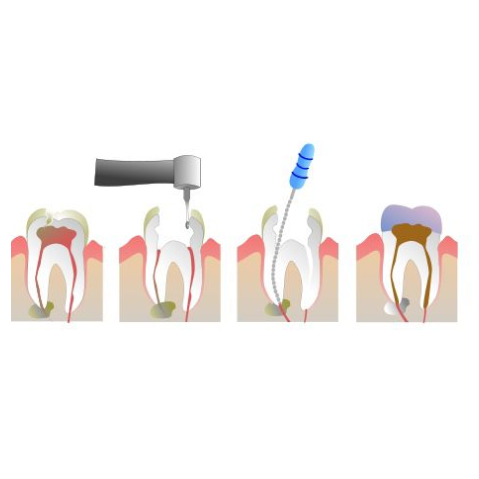

Signs You Need a Root Canal Treatment

It usually starts with something small. A slight discomfort while eating. A sharp feeling when something cold or hot touches your tooth. You ignore it. Because it’s not constant. It comes and goes. So it doesn’t feel serious. But then…it stays longer than it should. That same tooth starts reacting more often. The pain gets [...]

A Simple Guide to Root Canal Treatment and Dental Care

The words “root canal treatment” always seem to bring fear into people’s minds, especially because they associate it with pain.

Restore Your Tooth, Relieve Your Pain with Tooth Root Canal in Karachi at Altamash Dental Clinic

Tooth pain can be tough to ignore because it loudly impacts your mood, your eating habits, and even your daily routine